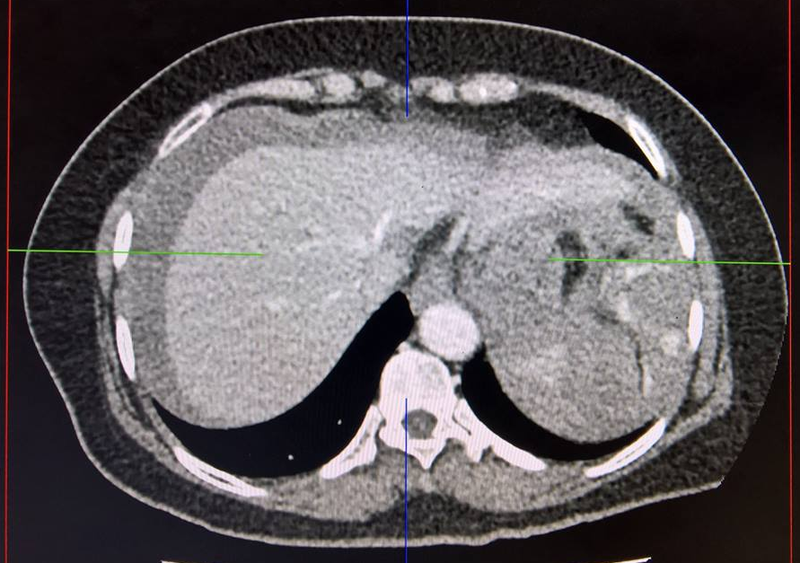

Chụp CT bụng là kỹ thuật sử dụng tia X quét qua bụng của bệnh nhân. Quy trình này diễn ra trong vài phút. Qua xử lý kỹ thuật, kết quả chụp cho ra những hình ảnh mặt cắt ngang ổ bụng dưới dạng 2D hoặc 3D, cho phép bác sĩ phát hiện được tình trạng bất thường của cơ xương khớp vùng bụng, các cơ quan, mạch máu, từ đó chẩn đoán được bệnh lý, nguyên nhân gây bệnh hay theo dõi bệnh trong quá trình điều trị.

Chụp CT bụng là gì? Cần lưu ý gì khi chụp và chi phí bao nhiêu? 2 Kết quả chụp CT bụng cho ra những hình ảnh mặt cắt ngang ổ bụng dưới dạng 2D hoặc 3D

Sau 60 - 90 phút, bạn sẽ nhận kết quả chụp CT bụng. Trường hợp cần các bác sĩ hội chẩn thì sẽ mất nhiều thời gian hơn mới nhận kết quả. Kết quả cho thấy sự bất thường khi hình ảnh thể hiện tình trạng viêm nhiễm, bệnh lý mạch máu vùng bụng, khối u trong các tạng ổ bụng… Lúc này, bác sĩ có thể sẽ hẹn bạn cần được kiểm tra thêm nhằm tìm hiểu kỹ hơn về vấn đề bạn đang mắc phải, từ đó có phương pháp điều trị phù hợp.